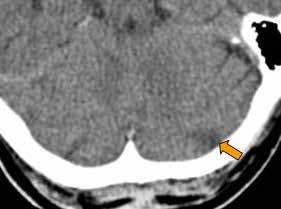

Zobje in telesni organi

Na sliki desno je shema povezav med zobmi in telesnimi organi, ki so jo naredili na Dr. Clark Research Slovenija (Drclark. si) po izsledkih več tisočletij starih spoznanj tradicionalne kitajske medicine. Denimo, levi zgornji modrostni zob (št. 28) je povezan z meridianom tankega črevesa in srca. Zaradi bolnega zoba in zatorej motenega pretoka čija čez ta meridian imamo lahko migrene, epilepsijo, težave s srednjim ušesom, rameni, komolcem, možgani, hrbtenjačo, krvjo, venami in arterijami. Njihova še podrobnejša shema, ki je dostopna na misteriji.si/blog/cat/pomoc_ pri_zdravju/, pa razkriva, da lahko to izzove tudi vremensko občutljivost, vremenski glavobol, mišično distonijo (krčenje mišic), multiplo sklerozo, možganski tumor, motnje vitalnosti, izostanek glasu po daljšem govoru, išias, glavobole, zvonjenje v ušesih, zamrznjeno ramo, vnetje obraznega živca, vnetje vidnega živca. Če je ta zob mrtev, pa so težave še toliko hujše.